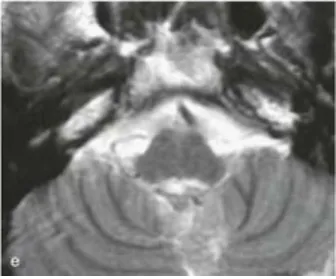

病例二:31岁男性患者

因颈部疼痛及步态共济失调就诊,术前MRI(a-c)显示第四脑室及背侧颅颈交界区存在巨大室管膜瘤。巴教授实施手术后,术后MRI(e)证实肿瘤全切,术后未出现新发神经功能缺损。